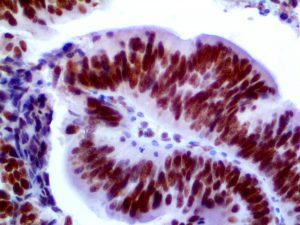

The first cytokines released are interleukin 1β (IL-1β) and tumor necrosis factor-α (TNF-α), which attract a variety of circulating white blood cells (WBCs) to the infection site, including neutrophils, monocytes, macrophages, and natural killer (NK) cells. This response, along with the antipathogenic chemicals released by these cells (i.e., complement), comprise the innate immune response. These cells directly attack the invading pathogen and also release additional cytokines, chief among them interleukin-1 and 6 (IL-6). IL-6 is essential for invoking the adaptive immune response, which calls T-cells, B-cells, and T helper (Th) cells to the infection site. IL-6 also stimulates further recruitment, proliferation and activation of macrophages.

This activation induces inflammatory monocytes to highly express IL-6, starting a localized and then systemic cascade effect that results in hyperproduction of IL-6, which accelerates the inflammatory process. Because IL-6 also increases vascular permeability, excessive levels cause blood vessels to become very leaky. This, along with clotting factors released from vascular endothelial cells, stimulates the coagulation cascade, resulting in microthrombosis (tiny clots), which leads to ischemia and tissue death of the kidney, intestines, heart, liver, brain and extremities.